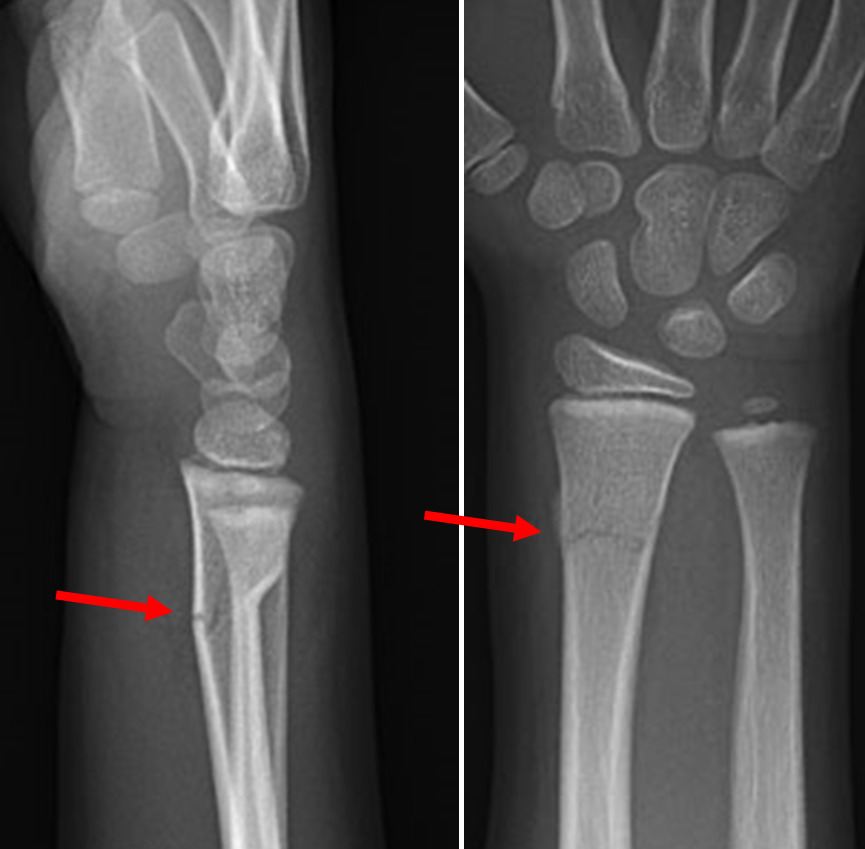

A male patient, aged 32 years old, sustained a left wrist fracture from …

Hand wrist fracture | Student Doctor Network

Wrist Fractures (Distal Radius Fractures) – Pro doctor

Premium Photo | Left wrist x-ray fracture raduis.

Wrist Fractures Information | Florida Orthopaedic Institute

Wrist Fractures (Distal Radius) – Hobart Orthopaedics

Distal radius fracture: causes, symptoms, conservative and surgical …

Distal Radius Fracture – Orthopedics – Medbullets Step 2/3